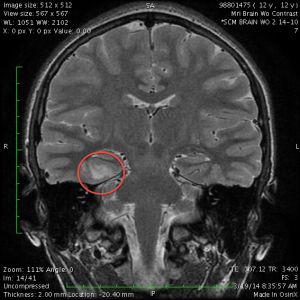

However, Dr. Cheshier’s manner made up for it. He patiently answered all of our questions, showed us the lesion on the MRI images, and talked about what the surgery would be like. He said that although the hippocampus was fairly close to the lesion, he was confident he would be able to resect the lesion without damaging the hippocampus. He said that this surgery had a 70% no-seizures-ever-again success rate, with another 20% chance of greatly reduced need for medication.